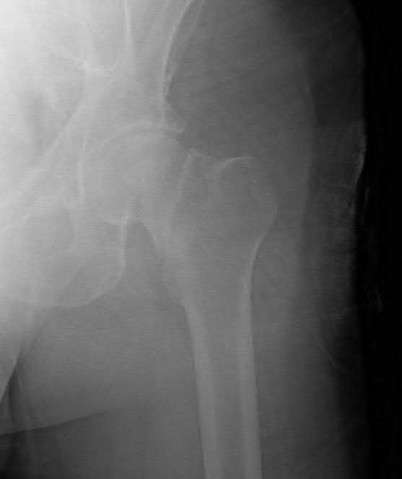

A 76-year-old male community ambulatory presented to clinic complaining of pain in the left groin that has been persistent for the last 8 months. Radiographs obtained from clinic are seen in Figure A. You suspect a femoral neck nonunion and obtain a CT scan which confirmed it. Which of the following statements is true?

A total hip arthroplasty (THA) after nonunion of a femoral neck fracture would provide the best long term outcomes in a 76-year-old male who is a community ambulator.

After nonunion of a femoral neck fracture, hemiarthroplasty and THA are good salvage option for the physiologically older patients. When deciding between these two options, THA is better for active and cognitively intact patients. THA is also indicated in patients with radiographic evidence of degenerative disease about the acetabulum. Hemiarthroplasty is advocated for patients who are older and less active.

Yang et al. retrospectively investigated the risk factors for nonunion in patients treated with cannulated screws. They reviewed 202 patients who had femoral neck fractures and were treated with internal fixation with cannulated screws. They identified that triangle configuration, displaced fracture, borderline or unacceptable reduction, and increased screw shaft subchondral purchase over the femoral neck were all risk factors for nonunion after internal fixation.

Inverted triangle configuration was found to increase rate of union.

Archibeck et al. retrospectively reviewed the outcomes of 102 THAs after failed internal fixation for a hip fracture (including both femoral neck and intertrochanteric). They concluded that the conversion of failed hip internal fixation has elevated risks compared to a primary THA, however, it may still be successful. The biggest concern for these patients postoperatively are periprosthetic fracture and dislocation.

Figures and Illustrations:

Figure A is an AP pelvic radiograph demonstrating a nonunion of a femoral neck fracture after suboptimal fixation with 3 cannulated screws in a triangle configuration.

Illustration A is an AP radiograph of the left hip in this patient following conversion to THA.

Illustration B is a radiograph demonstrating a valgus osteotomy. Illustration C shows an example of a femoral neck nonunion with varus malreduction.